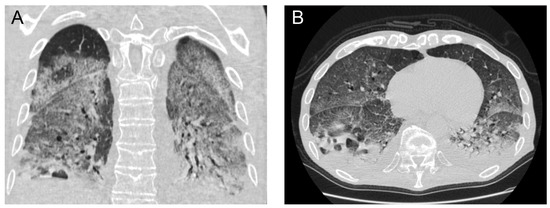

Laboratory investigations showed normal lymphocyte count with neutrophilia (89%) and severe lymphopenia (4.9%), increased C reactive protein (CRP) at 10.3 mg/L and normal procalcitonin (PCT) at 0.82 µg/dL. The rest of his laboratory values were within the normal range. His chest X-ray on admission presented with extensive consolidation and infiltrates mainly in the lower lung fields with blunting of the costo-diaphragmatic angles. His admission chest computed tomography (CT) scan demonstrated extensive ground glass infiltrates and diffuse consolidation bilaterally with a focus on the right lower lobe (Figure 1).

Figure 1.

Initial (on admission) chest computed tomography scan in coronal (A) and axial (B) views demonstrating extensive bilateral areas of consolidation and ground glass infiltrates, with lung cavitation mainly on the posterior segment of the right lower lobe.

The patient’s initial chest CT demonstrated significant areas of diffuse consolidation and patchy ground glass opacification. These are findings which have previously been associated and described with COVID-19 viral pneumonia [7]. In addition, in hindsight there seemed to be a focus of atelectasis and consolidation in the right lower lobe which could represent the precursor of the lung abscess.